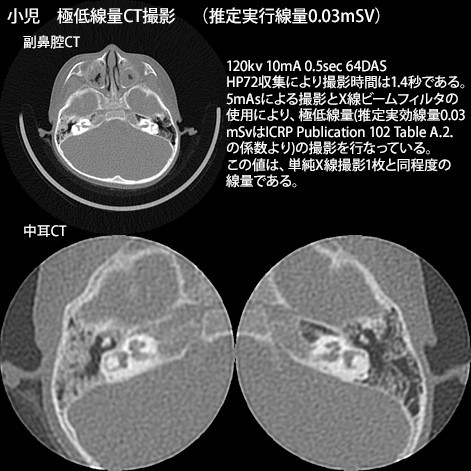

64列の強みを生かし、短時間での撮影を行うことで患者さんの負担を軽減し、耳の疾患に対しては0.5m撮影にて、微細な構造を描出します。また、被曝低減フィルターと逐次近似再構成法により、小児でも極低線量ながら、診断に十分な画像を提供します。

『小児』のX線撮影